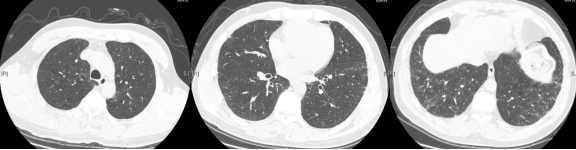

病例:男,23岁,咳嗽8月伴气短6月,患者在硬质合金刀具厂工作3年,接触粉尘:

ero为什么不显示叶俏教授:HRCT是发现和鉴别「过敏性肺炎」的重要环节,何种表现指向预后不良?使患者发病的危害因素躲在哪些环境中?_https://www.jmylbn.com_新闻资讯_第45张

脱离暴露7月后:[32]

ero为什么不显示叶俏教授:HRCT是发现和鉴别「过敏性肺炎」的重要环节,何种表现指向预后不良?使患者发病的危害因素躲在哪些环境中?_https://www.jmylbn.com_新闻资讯_第46张

这时需要进一步肺脏活检来证实,所以环境的暴露评估也非常重要。